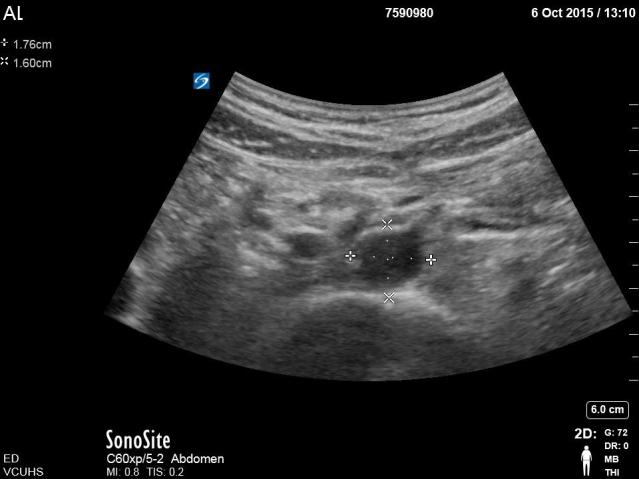

A. Measurement of proximal aorta in cross-section from outer to outer wall + clip scanning through